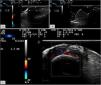

The 2nd patient was a 72-year-old woman presenting with a long-standing periungual nodule that was intermittently painful. She reported no changes in size or consistency and no drainage. Examination showed a well-defined, firm 5-mm subcutaneous nodule on the proximal nail fold of the 2nd finger of her right hand, with normal overlying skin. Ultrasound with an 18-MHz probe revealed the presence of a 5.6mm×1.6mm hypoechoic mass on the proximal nail fold, overlying the nail plate, without matrix involvement and minimal basal vascularity (Fig. 2A). With a presumptive diagnosis of acquired digital fibrokeratoma, excision was performed, and histology confirmed a periungual fibrokeratoma.

(A) Hypoechoic 5.6mm×1.6mm mass on the proximal nail fold overlying the nail plate without matrix involvement and minimal basal vascularity. (B) Well-defined 5.2mm×2.8mm hypoechoic lesion. (C) Frontal view of a 1.5-mm hyperechoic lesion, unrelated to underlying structures and without Doppler flow.